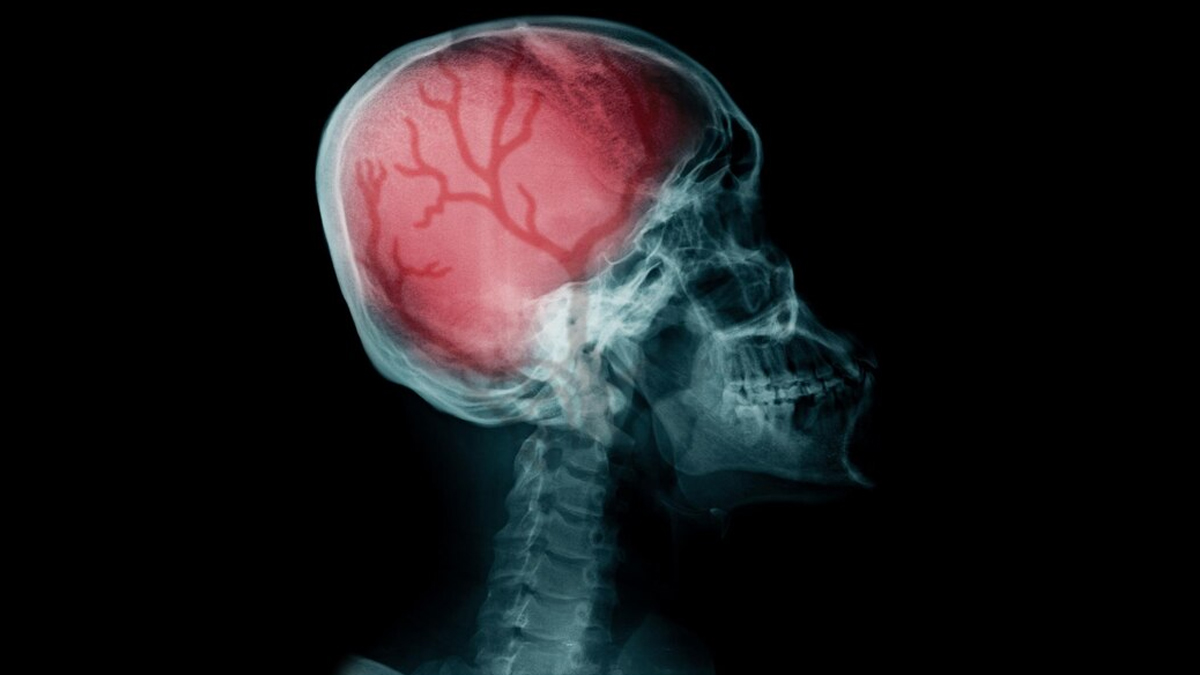

The brain is the most essential organ of our body and is also the most fragile and complex. That is why head traumas should not be taken lightly and should be looked at by a credible doctor promptly. Timely intervention can help prevent serious brain damage and be life-saving.

Explaining the probable cause, Dr Tyagi said, “The problem with brain injury is that the neurons do not recover or regenerate. So, the part of the brain that was damaged suffers a lasting or in some cases, permanent deficit. It depends on what area of the brain was involved in the injury.”